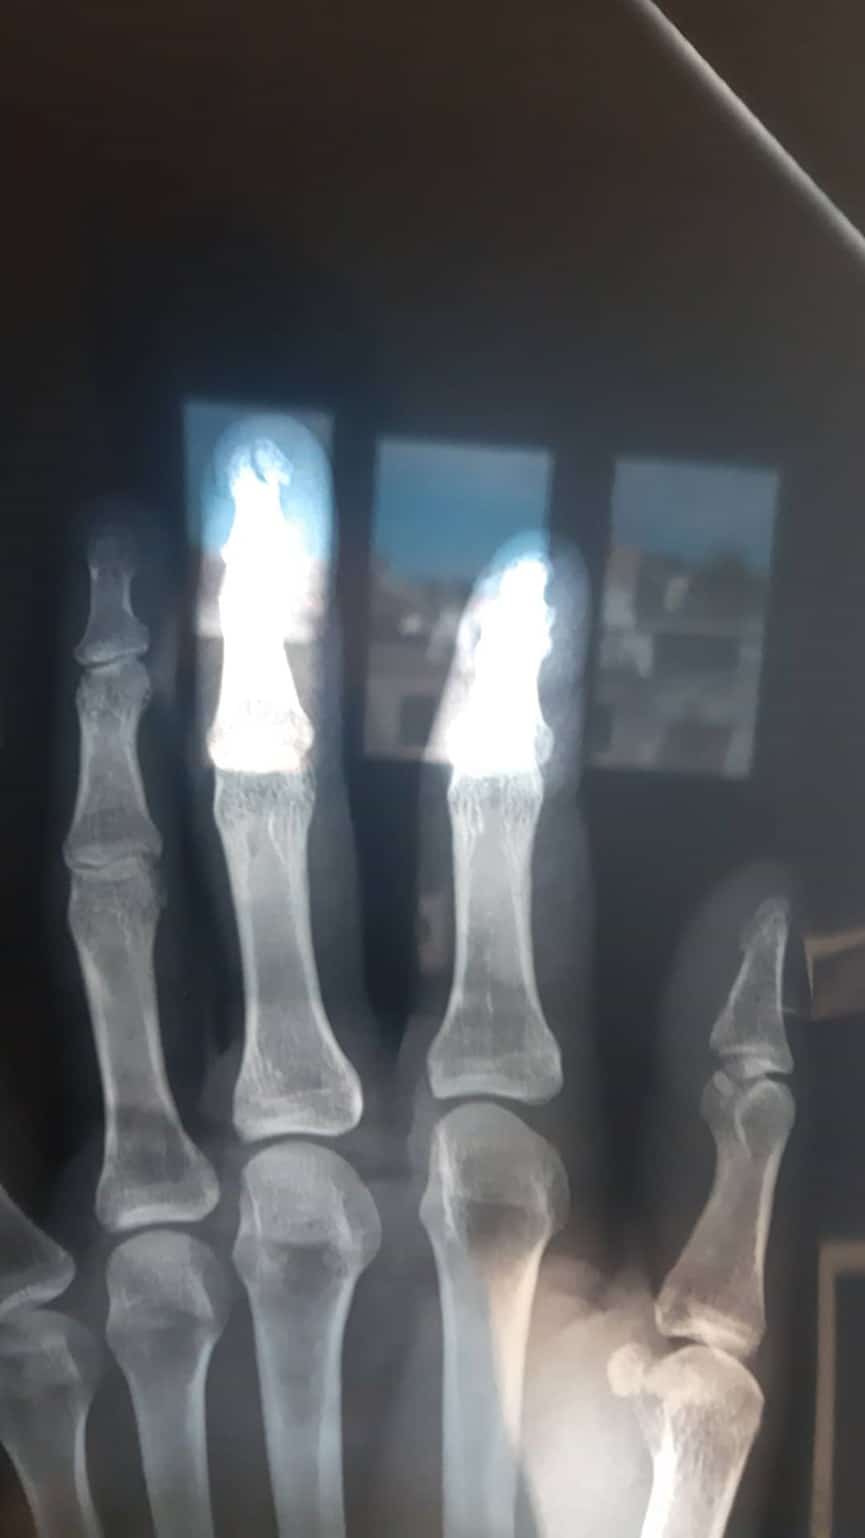

Πιο συγκεκριμένα, η Μαρία Λαζαρίδου έσπασε το μεσαίο δάχτυλο του αριστερού της χεριού με αποτέλεσμα να έχει αφόρητους πόνους. Λόγου του ιδιαίτερου σημείου μάλιστα, οι γιατροί της είπαν πως δε μπορούν να το δέσουν.

Η πρώην παίκτρια του MasterChef ανέβασε παράλληλα και μια φωτογραφία με την ακτινογραφία που της έγινε στο νοσοκομείο.